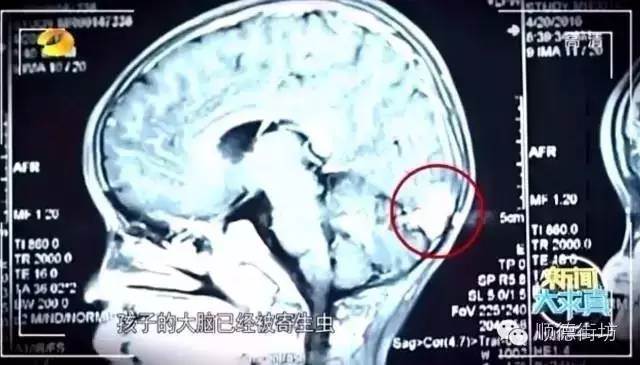

這個孩子也是經常吃不熟的食物,腦部被寄生蟲「啃」出一個洞▼